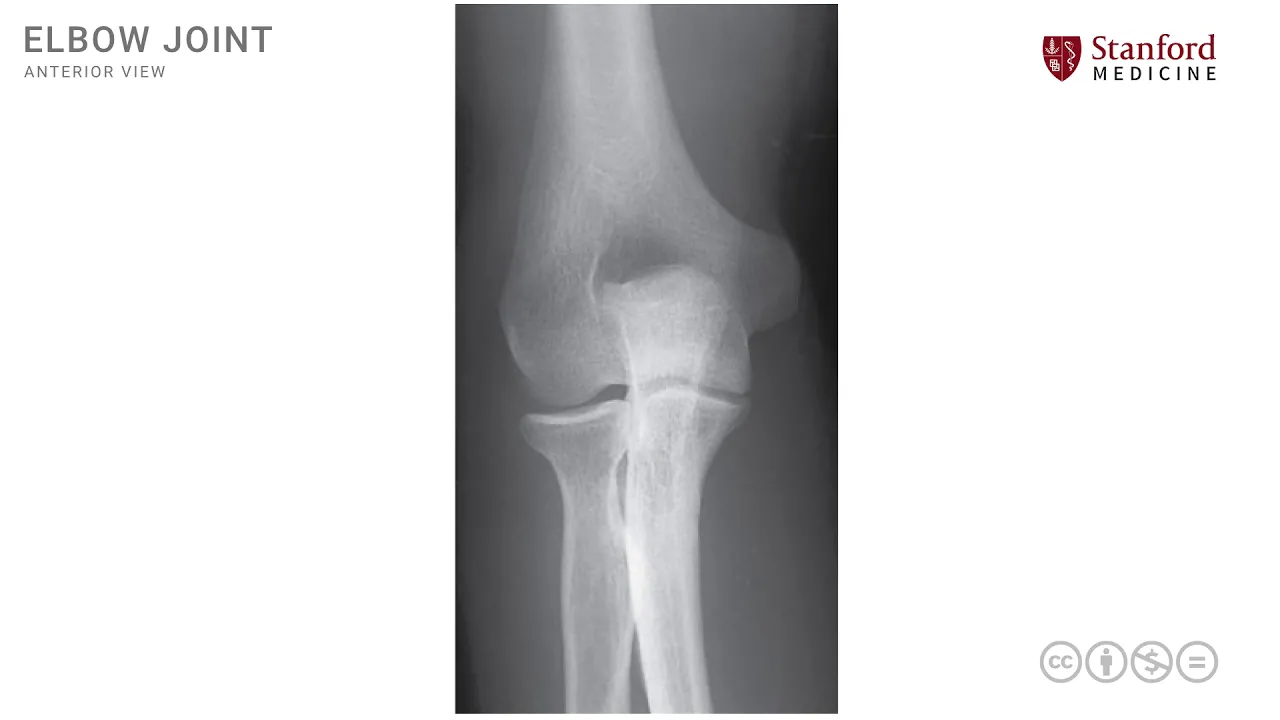

here we have an x-ray of the elbow joint and this is seen from a lateral view here and we see the three bones again that participate in the formation of the elbow joint this is the distal end of the humerus seen here and we also have the proximal end of the radius seen here and the proximal end of the ulna seen here these are the three bones that participate in the formation of the hinge joint which is what an elbow joint is let's now also look at those bony prominences that we looked at earlier this

is the coronoid process which is part of the proximal end of the ulna which is right here and see how it articulates with the distal end of the humerus we can also see the radial head seen here which is the proximal end of the radius and also articulating with that distal humerus note that the coronoid process and the radial head in this view this lateral view overlap to some extent and much of the radial head seems to be hidden by the coronoid process we also can see another part of the proximal elma ulna which is

known as the olecranon process which is a large bony extension of the proximal ulna seen here this is the electron process that had been outlined so nicely here and note that the olecranon process extends posteriorly it goes behind or posterior to the Condillac condylar processes of the distal humerus any of these three processes the olecranon process or the coronoid process or the radial head can be fractured and in injuries around the elbow joints these fractures are commonly identified [Music] you